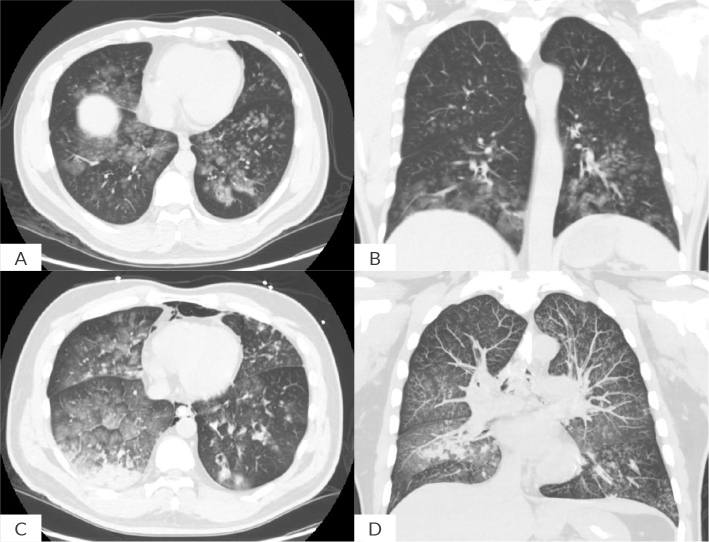

Histoplasma capsulatum is a dimorphic fungus that grows as a mould in the environment and as a yeast in human tissues causing histoplasmosis. Histoplasmosis varies in clinical presentations and severities of the illness and is endemic in certain areas of North, Central, and South America, Africa, and Asia. A 47-year-old previously healthy male presented with a sudden onset of massive haemoptysis requiring emergent intubation in the emergency department. Bronchoscopy revealed blood clots within the endotracheal tube extending into both main bronchi with active bleeding from both airways. Subsequently, the patient experienced a cardiac arrest with asystole, requiring three rounds of cardiopulmonary resuscitation before achieving return of spontaneous circulation. A computed tomography scan of the chest demonstrated diffuse ground-glass opacities. Collateral information obtained from the patient's family indicated travel to Southeast China two months prior to hospitalization. Histoplasma antigen testing returned positive, and antifungal therapy was initiated. Along with serial suctioning and forceps use via fibreoptic bronchoscopy, cryoextraction of blood clots from the bronchi was performed, leading to successful extubation and hospital discharge. This case highlights the need to consider histoplasmosis in patients who have travelled to endemic areas and present with severe respiratory symptoms.

Abstract Image